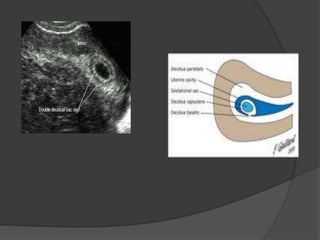

 1- Double decidual sac Sign (DDSS) : is the earliest

sign of IUP seen by 4-5 wks from LMP by TV U/S

formed of two echogenic rings and it’s where the

fertilized ovum implants itself into the decidualized

endometrium and formed of :

- Decidua Parietalis : outer ring lining uterine cavity

- Decidua capsularis : Inner ring covering the free

margin of the G.S

- Decidua Basalis : which the endometial base of the

sac

Decidua basalis + chorion frondosum = placenta

Normal imaging milestones 1- Double decidual sac Sign (DDSS) : is the earliest sign of IUP seen by 4-5 wks from LMP by TV U/S formed of two echogenic rings and it’s where the fertilized ovum implants itself into the decidualized endometrium and formed of : - Decidua Parietalis : outer ring lining uterine cavity - Decidua capsularis : Inner ring covering the free margin of the G.S - Decidua Basalis : which the endometial base of the sac Decidua basalis + chorion frondosum = placenta